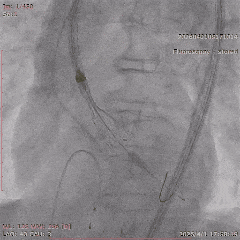

进一步评估显示,患者瓣膜狭窄程度重,瓣叶钙化明显,左心室腔径偏小,手术中对器械通过、瓣膜释放以及循环稳定性的要求都更高。团队结合术前影像和整体身体状况,制定了周密的介入治疗方案,并做好相关风险预案。

手术过程

手术当天,团队顺利完成经导管主动脉瓣置换术。术中瓣膜释放位置理想,人工瓣膜功能良好,未见明显瓣周漏,也未出现严重传导阻滞、恶性心律失常等情况,患者术后安返CCU病房。

▲导丝跨瓣

▲18mm球囊预扩

▲输送器过弓

▲瓣膜定位

▲释放至工作位

▲工作位造影

▲脱钩

▲20mm球囊后扩

▲最终造影

术后复查